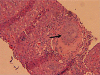

Systemic sarcoidosis is a disease of unknown etiology, with the liver being the third most commonly affected organ. Most cases of hepatic sarcoidosis are not clinically apparent, but a few can progress to liver cirrhosis, portal hypertension and ultimately liver failure. The diagnosis of hepatic sarcoidosis is difficult, considering that no single laboratory test or radiographic finding can definitively diagnose this systemic disease. Diagnosis of hepatic sarcoidosis relies heavily on histopathologic evaluation of two or more organs, a diagnostic modality that is invasive and may not be applicable to all patients. The treatment of hepatic sarcoidosis is challenging, with no large randomized controlled trials done to date. Physicians must be aware of the complications of hepatic sarcoidosis, and must include the same in the differential diagnosis of liver cirrhosis. We present a case of hepatic sarcoidosis complicated by portal hypertension and liver cirrhosis.